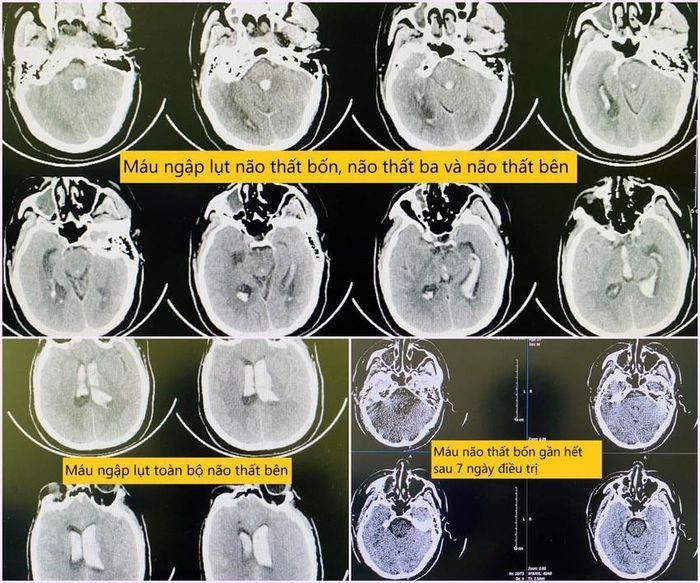

Hình ảnh chụp phim sọ não khi bệnh nhân nhập viện và sau quá trình điều trị.

Các bác sĩ tiến hành chụp phim sọ não có dựng mạch xác định căn nguyên và đánh giá tổn thương, nhằm có chiến lược điều trị tối ưu.

“Kết quả về cho thấy hình ảnh chảy máu khủng khiếp, "ngập lụt" toàn bộ não thất bên, não thất ba, não thất tư, gây giãn não thất cấp, gây tắc nghẽn lưu thông hệ thống não thất. Với mức độ tổn thương như này nếu không can thiệp gần như chắc chắn tử vong”- bác sĩ Trung tâm Đột quỵ thông tin.